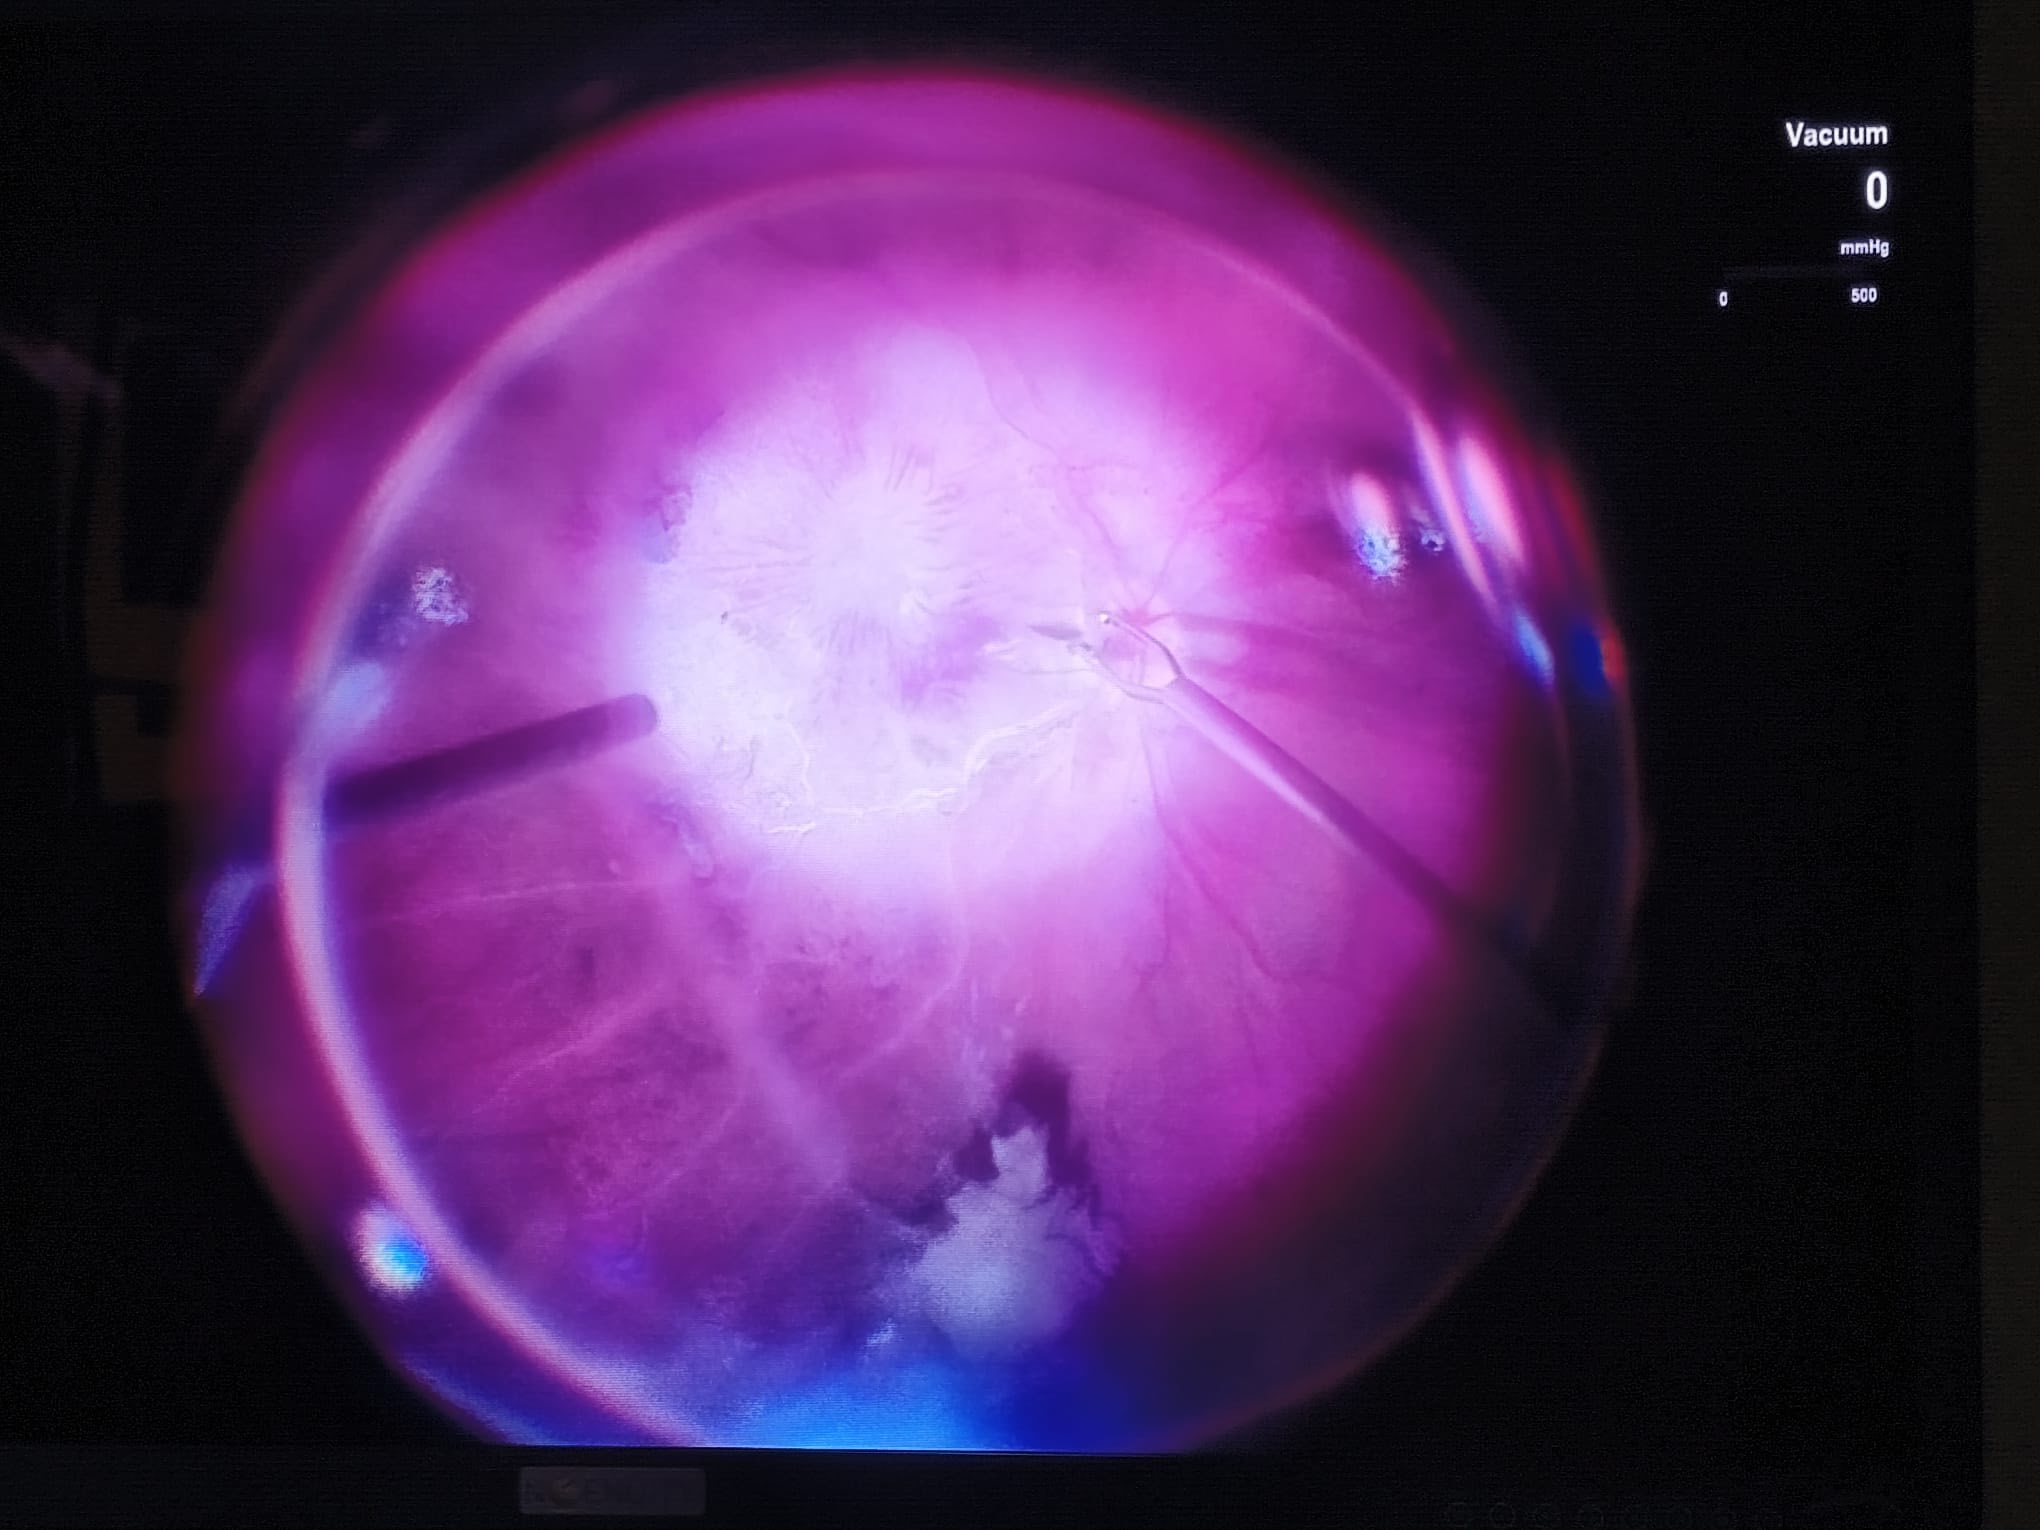

De departe, cel mai dificil caz chirurgical de la începutul acestei săptămâni a fost un caz de hemoftalmus de azi (umplerea cavității ochiului cu sânge – în acest caz fiind de etiologie neprecizată preoperator), hemoftalmus care s-a dovedit a fi asociat și cu o dezlipire de retină localizată în jurul unei mici zone de dializă retiniană.

Intraoperator, cauza sângerării masive intraoculare a ieșit la iveală: o ocluzie de ram venos superi-temporal retinian (un fel de “infarct” al unei părți din retină), vasele supero-temporale apărând complet obstruate, fără conținut sanguin, ca niște “sârme” albe, strălucitoare.